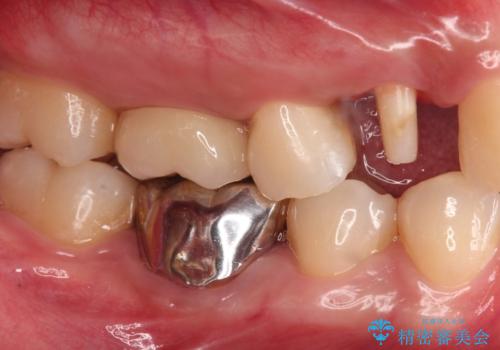

- 右上4 253,000円(部分矯正(エクストリュージョン):110,000円 歯周外科治療:エクストリュージョン代に含まれます 根管治療:保険 ファイバーコア:22,000円 仮歯:11,000円 ジルコニアクラウン:110,000円)費用は治療当時の料金となります

保険適用内だと抜歯の選択肢しかないような歯でも保険外の治療をすると残すことができる場合があります。

歯を抜かずに良い状態で保存できたことで大変喜んでいただけました。